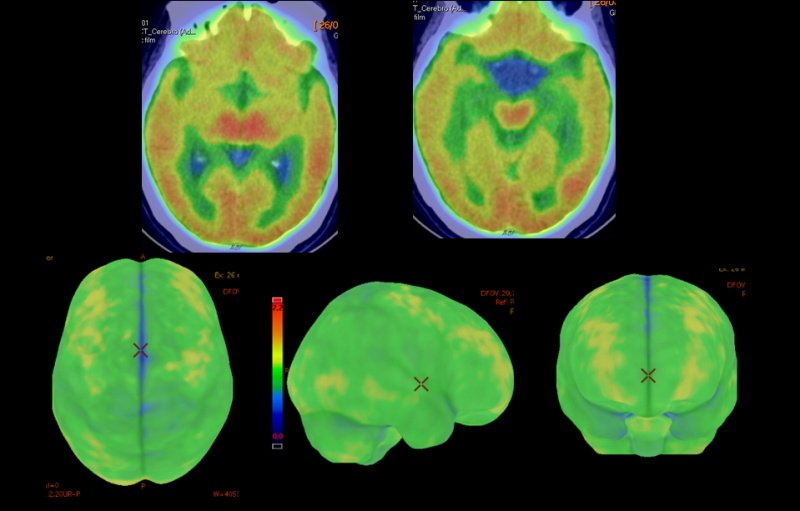

Se complementó con estudio PET Beta- amiloide (18F-Florbetaben). En las imágenes precoces post-inyección que aportan información de la perfusión cerebral, no se apreciaron alteraciones significativas en las diferentes estructuras corticales que conforman ambos hemisferios cerebrales, así como tampoco a nivel subcortical ni en fosa posterior (fig 3). En las imágenes tardías post-inyección que informan sobre la densidad de placa neurítica de beta-amiloide (fig. 4) se observó pérdida de la diferenciación entre sustancia gris y sustancia blanca en todas las regiones claves. La sustancia gris de dichas regiones muestra una importante captación del trazador, superior a la de la sustancia blanca, abarcando la mayoría de los cortes y en algunas zonas llegando incluso al margen cortical exterior. Presenta una puntuación CCRT (captación cortical regional de trazador) de 3. El estudio se considera globalmente como positivo con un CPAE grado 3 (exploración con depósitos importantes de beta-amiloide).